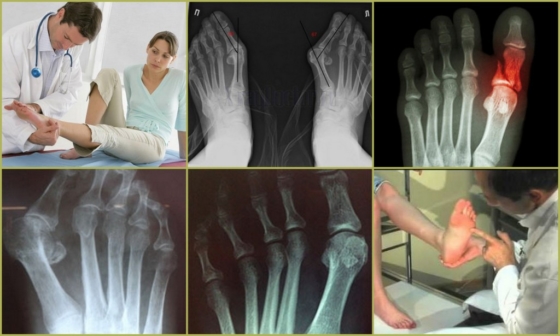

Симптоматические проявления деформации Тейлора представлены ниже на фото.

Для того, чтобы избавиться от проблемы, важна диагностика заболевания, которую проводит ортопед. Он тщательно осматривает все части ног на наличие искривлений, сопутствующих патологий, определяет точную локализацию боли, оценивает свободу движений по отношению к середине стопы. Для точного обнаружения степени деформации Тейлора необходимо проведение рентгенографического исследования, которое позволяет определить:

- Имеется ли деформация Тейлора;

- Насколько увеличен угол между мизинцем и четвертым пальцем;

- Наличие бокового отклонения;

- Увеличенную головку косточки плюсны;

- Имеется ли артроз;

- Имело ли место травмирование сустава.